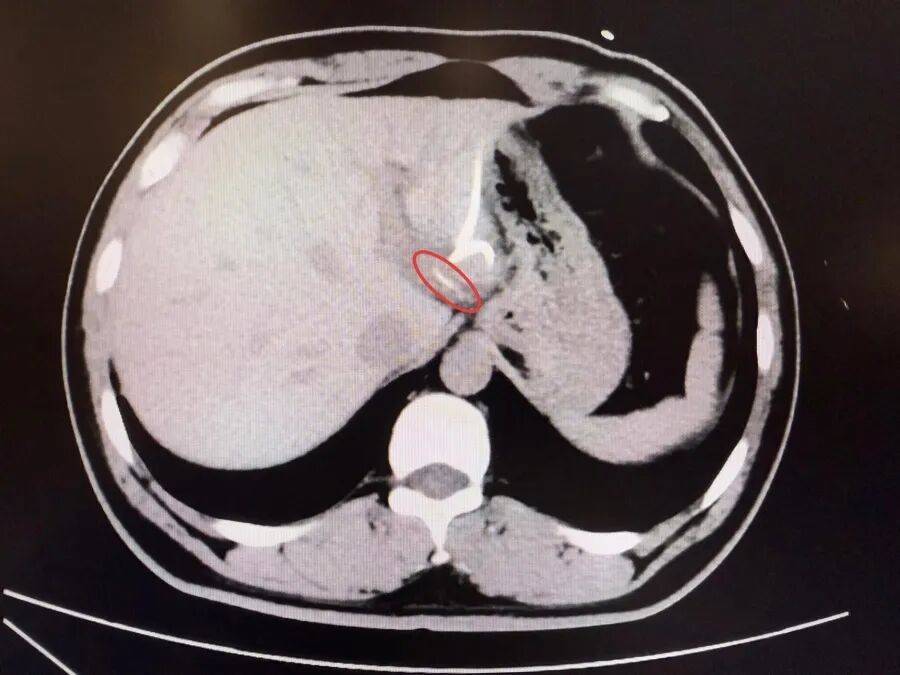

半月前,37岁的李先生(化名)误吞鱼刺却未察觉,数天后出现腹痛、高热(达40℃)等症状,当地医院诊断为“肝脓肿”,治疗后症状反复,CT检查才发现肝脏左叶有鱼刺——其已穿透胃壁入肝引发感染,十分危险,当地医生评估后认为,要彻底清除异物,需要进行左半肝切除手术,这让李先生难以接受。

为寻求更精准、微创的治疗,李先生转至复旦大学附属中山医院内镜中心。“鱼刺位置非常凶险,就在贲门旁刺入左肝,紧贴大血管。”接诊的周平红主任指出,鱼刺位于贲门旁左肝处,紧贴大血管,且腹腔感染粘连严重,手术难度极高。